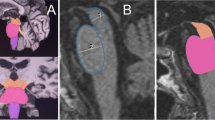

We then performed shape analysis in the most predictive regions, namely the hippocampus (PD vs PDD) and globus pallidus (PDD vs DLB) (see Fig. 2a, b).

Shape analysis of hippocampi and pallidi in α-synucleinopathies. a Dorsal and ventral view of left and right hippocampus in the PDD <PD contrast. b dorsal and ventral view of left and right globus pallidus in the DLB <PDD contrast. Light blue structure shape, orange shape difference. p < 0.05 FDR corrected. A anterior, P posterior, L left, R right

Both left and right hippocampi showed supra-threshold differences in the PDD < PD contrast, with left hippocampus being extensively affected by regional atrophy in its dorsolateral and ventrolateral surfaces. No significant shape alterations were found for the opposite contrast (PDD greater than PD).

DLB patients showed deformation of both dorsal and ventral pallidal surface when compared to PDD. No significant deformations in the PDD < DLB contrast were found.